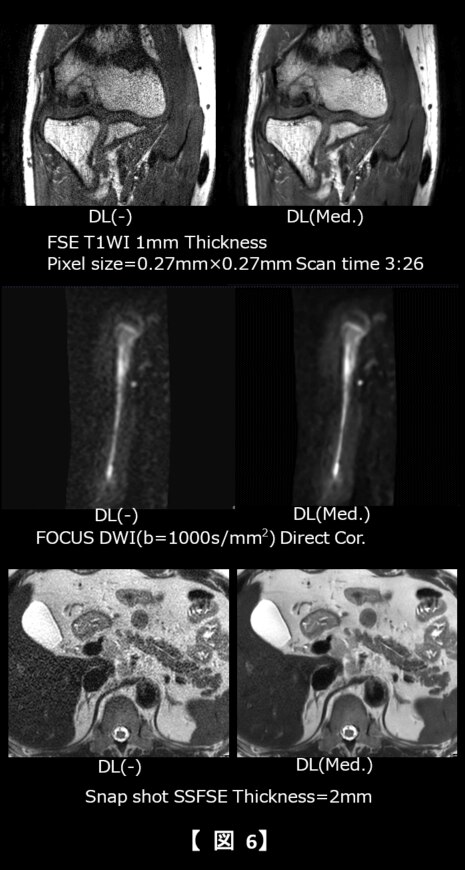

頭部領域では、脳や眼窩領域の従来より薄いスライス厚を臨床上現実的な撮像時間で、下垂体領域では従来より高SNRで収集することが可能となり(図5)、整形領域ではオフセンターの高SNR・高分解能画像に加え、低SNRのDWIにおいてもSNRを向上させることで診断能の向上に寄与していると考えられる(図6中段)。また腹部の膵管領域においても高空間分解能に撮像することが可能となった。さらにBWを広帯域化することでケミカルシフトの低減と高空間分解能かつ高SNR画像の両立が期待できる(図6下段)。